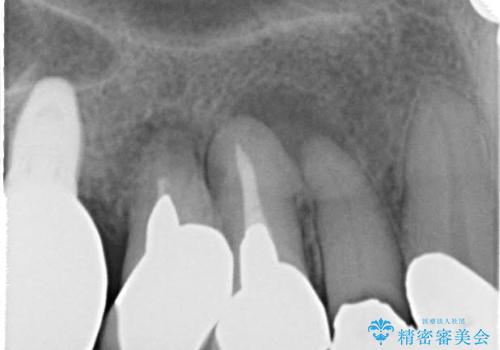

- 歯周外科・再根管治療後、クラウンを製作する。

歯周病治療の注意事項(リスク・副作用など)

- 外科手術のため、術後に痛みや腫れ、違和感を伴います

- 歯周組織再生治療は患者様の状態によって術後の経過が異なります(見た目が改善しない場合もあります)

- 歯周組織再生治療は自費診療(保険適用外)となります